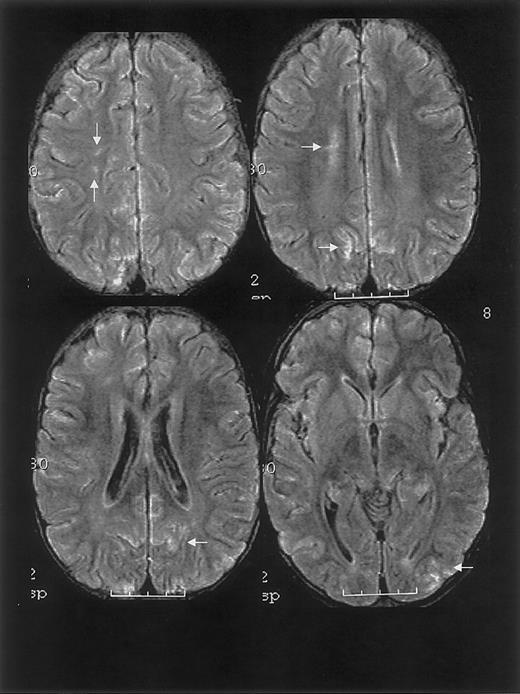

RPLS is difficult to distinguish from acute cerebral infarcts clinically and radiographically. The distinction is important because cerebral infarction implies irreversible damage and warrants blood transfusion therapy for an indefinite period. Conversely, RPLS is potentially reversible but may require judicious hypertensive management. In this case series, 2 patients were originally diagnosed as having cerebral infarcts according to the clinical reading of the MRI, one of whom was subsequently determined to have RPLS and the other with cerebral hemorrhage. Appropriate MRI techniques and interpretation play a key role in differentiating RPLS from cerebral infarct (Figure 4). Both RPLS and cerebral infarct present with T2-weighted hyperintensities. DWIs typically show hyperintense signal in cerebral infarcts, whereas DWIs in RPLS are ambiguous because of T2 shine-through effects.8 14 Producing images of the diffusion coefficient eliminates this ambiguity.

Characterization of T2-weighted hyperintensities on MRI of the brain distinguishing cerebral infarct from reversible posterior leukoencephalopathy syndrome (RPLS).

DWI indicates diffusion weighted image; DC, diffusion coefficient.